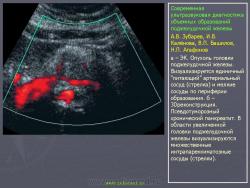

В большинстве (50-80%) случаев опухоль поражает головку ПЖ. Наиболее характерным признаком опухоли является локальное увеличение или выбухание контура какой-либо части железы. Маленькие опухоли достаточно легко визуализируются в головке, так как, во-первых, четкое изображение головки получить легче по сравнению с другими частями железы, а во-вторых, при расположении опухоли в головке обычно быстро развивается сдавление общего желчного протока с развитием соответствующей сонографической и клинической симптоматики. С другой стороны, опухоли небольших размеров в хвосте выявляются значительно реже. О возможном наличии опухоли свидетельствует также нарушение общей гармоничной формы ПЖ, увеличение размеров какого-либо ее отдела. Следует помнить о возможности инвазии всей ПЖ опухолью, имеющей мультицентричный рост. В этом случае наблюдается картина, схожая с диффузным отеком при остром панкреатите [4].

В большинстве случаев опухоль ПЖ выявляется как гипоэхогенное образование, почти лишенное внутренних эхоструктур. Однако встречаются опухоли с диффузно разбросанными эхосигналами и с эхосигналами высокой интенсивности в центре при их отсутствии на периферии. Несмотря на то что граница между опухолью и остальной паренхимой железы нечеткая, ее всегда можно приблизительно провести за счет разности в эхогенности нормальной ткани ПЖ и опухолевого очага. Хотя гипоэхогенная структура ткани опухоли, особенно при отсутствии мелких участков повышенной плотности в ней, напоминает таковую при кистах, отсутствие эффекта дистального усиления позволяет исключить жидкостный характер образования. Для кист, кроме того, характерна гораздо более ровная и четкая граница. В большинстве случаев опухолей в головке ПЖ визуализируется расширенный ГПП, причем в отличие от ХП стенки его ровные и неуплотненные. В случае, если диаметр расширенного ГПП составляет половину толщины железы или более, вероятность его обструкции опухолью очень велика. Наряду с ГПП дилатации могут подвергаться общий желчный проток и внутрипеченочные желчные протоки. Расширение ГПП и общего желчного протока наблюдается также и при препятствии, обтурирующем просвет общего желчного протока в области фатерова соска. Как было указано выше, визуализация ГПП в пределах гипоэхогенной зоны свидетельствует в пользу локального отека и против опухоли. Не следует забывать о возможности выявления типичных признаков ХП, а также псевдокист, расположенных дистальнее места опухолевой обструкции и являющихся следствием этой обструкции. Сдавление нижней полой и верхней брыжеечной вен и их дорсальное смещение характерно как для ХП, так и для опухоли, но в последнем случае оно более выражено. Для локализации опухоли в крючковидном отростке характерно смещение верхней брыжеечной вены, а иногда и головки ПЖ, в вентральном направлении. Обнаружение внутрипеченочных метастазов, увеличения чревных, перипортальных и забрюшинных лимфоузлов свидетельствует в пользу рака ПЖ [7].